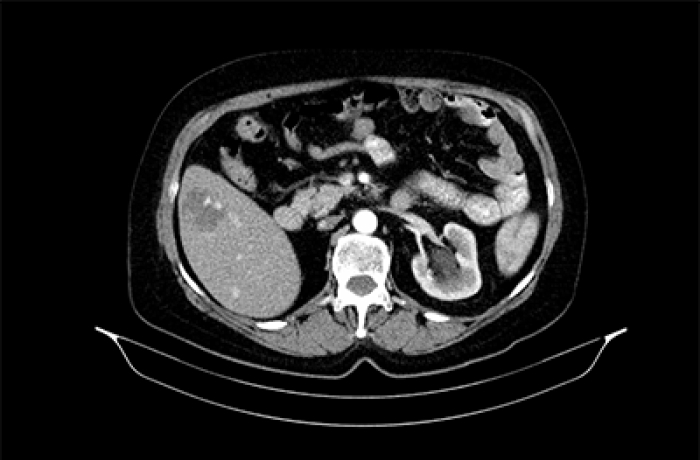

МСКТ с контрастированием - способ повысить чувствительность и специфичность исследования с помощью внутривенного введения йодсодержащего контрастного вещества. Такие препараты увеличивают рентгеновскую плотность органов и тканей, способны накапливаться в них с определенной динамикой, выполняют просветы сосудов. При исследовании органов брюшной полости и забрюшинного пространства используется комбинация внутривенного и перорального контрастирования, что позволяет максимально эффективно дифференцировать изменения в различных структурах и получать дополнительную информацию при некоторых заболеваниях полых органов. Контрастирование лежит в основе МСКТ-ангиографии - одного из важнейших методов диагностики сосудистых патологий. Контрастирование часто применяется для уточнения информации при МСКТ головного мозга, органов шеи, органов грудной клетки, органов брюшной полости и забрюшинного пространства, органов мочевыделительной системы; существуют методики МСКТ-ангиографии головного мозга, сосудов шеи (брахиоцефальные артерии), аорты (грудная, брюшная), верхних и нижних конечностей.

Несмотря на то, что МСКТ является достаточно информативным методом обследования, часто возникает необходимость получения более точных данных о конкретных патологических процессах или об особенностях состояния кровеносной системы на пораженном участке. Для этих целей и проводят контрастную компьютерную томографию.

Контрастное вещество представляет собой препарат, содержащий йод, благодаря чему усиливается поступающий от вен и артерий сигнал. В результате на экране монитора отображается точная картинка тканевых структур исследуемого органа.

После введения в вену препарата, контрастное вещество поступает непосредственно в кровоток и направляется в сердце, затем уже начинает циркулировать по всем сосудам в организме. Те органы, которые заполняются контрастом, на рентгене отображаются как белое пятно.